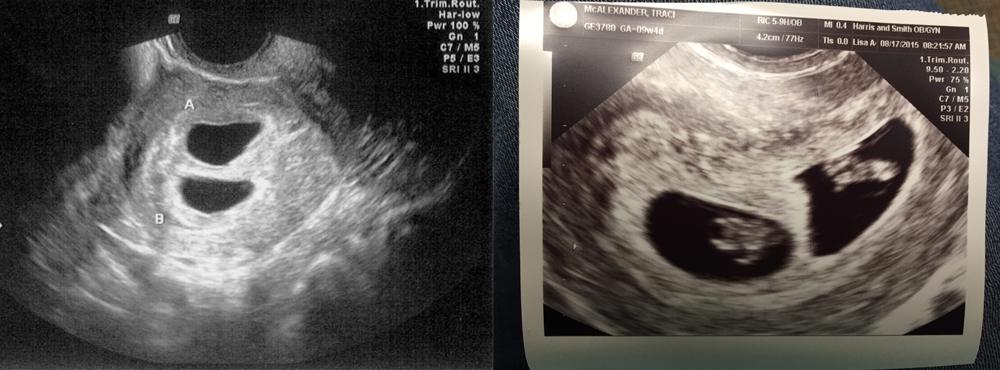

УЗИ двухплодной беременности на 5 неделе: Подборка изображений

Раздел: Калейдоскоп образов